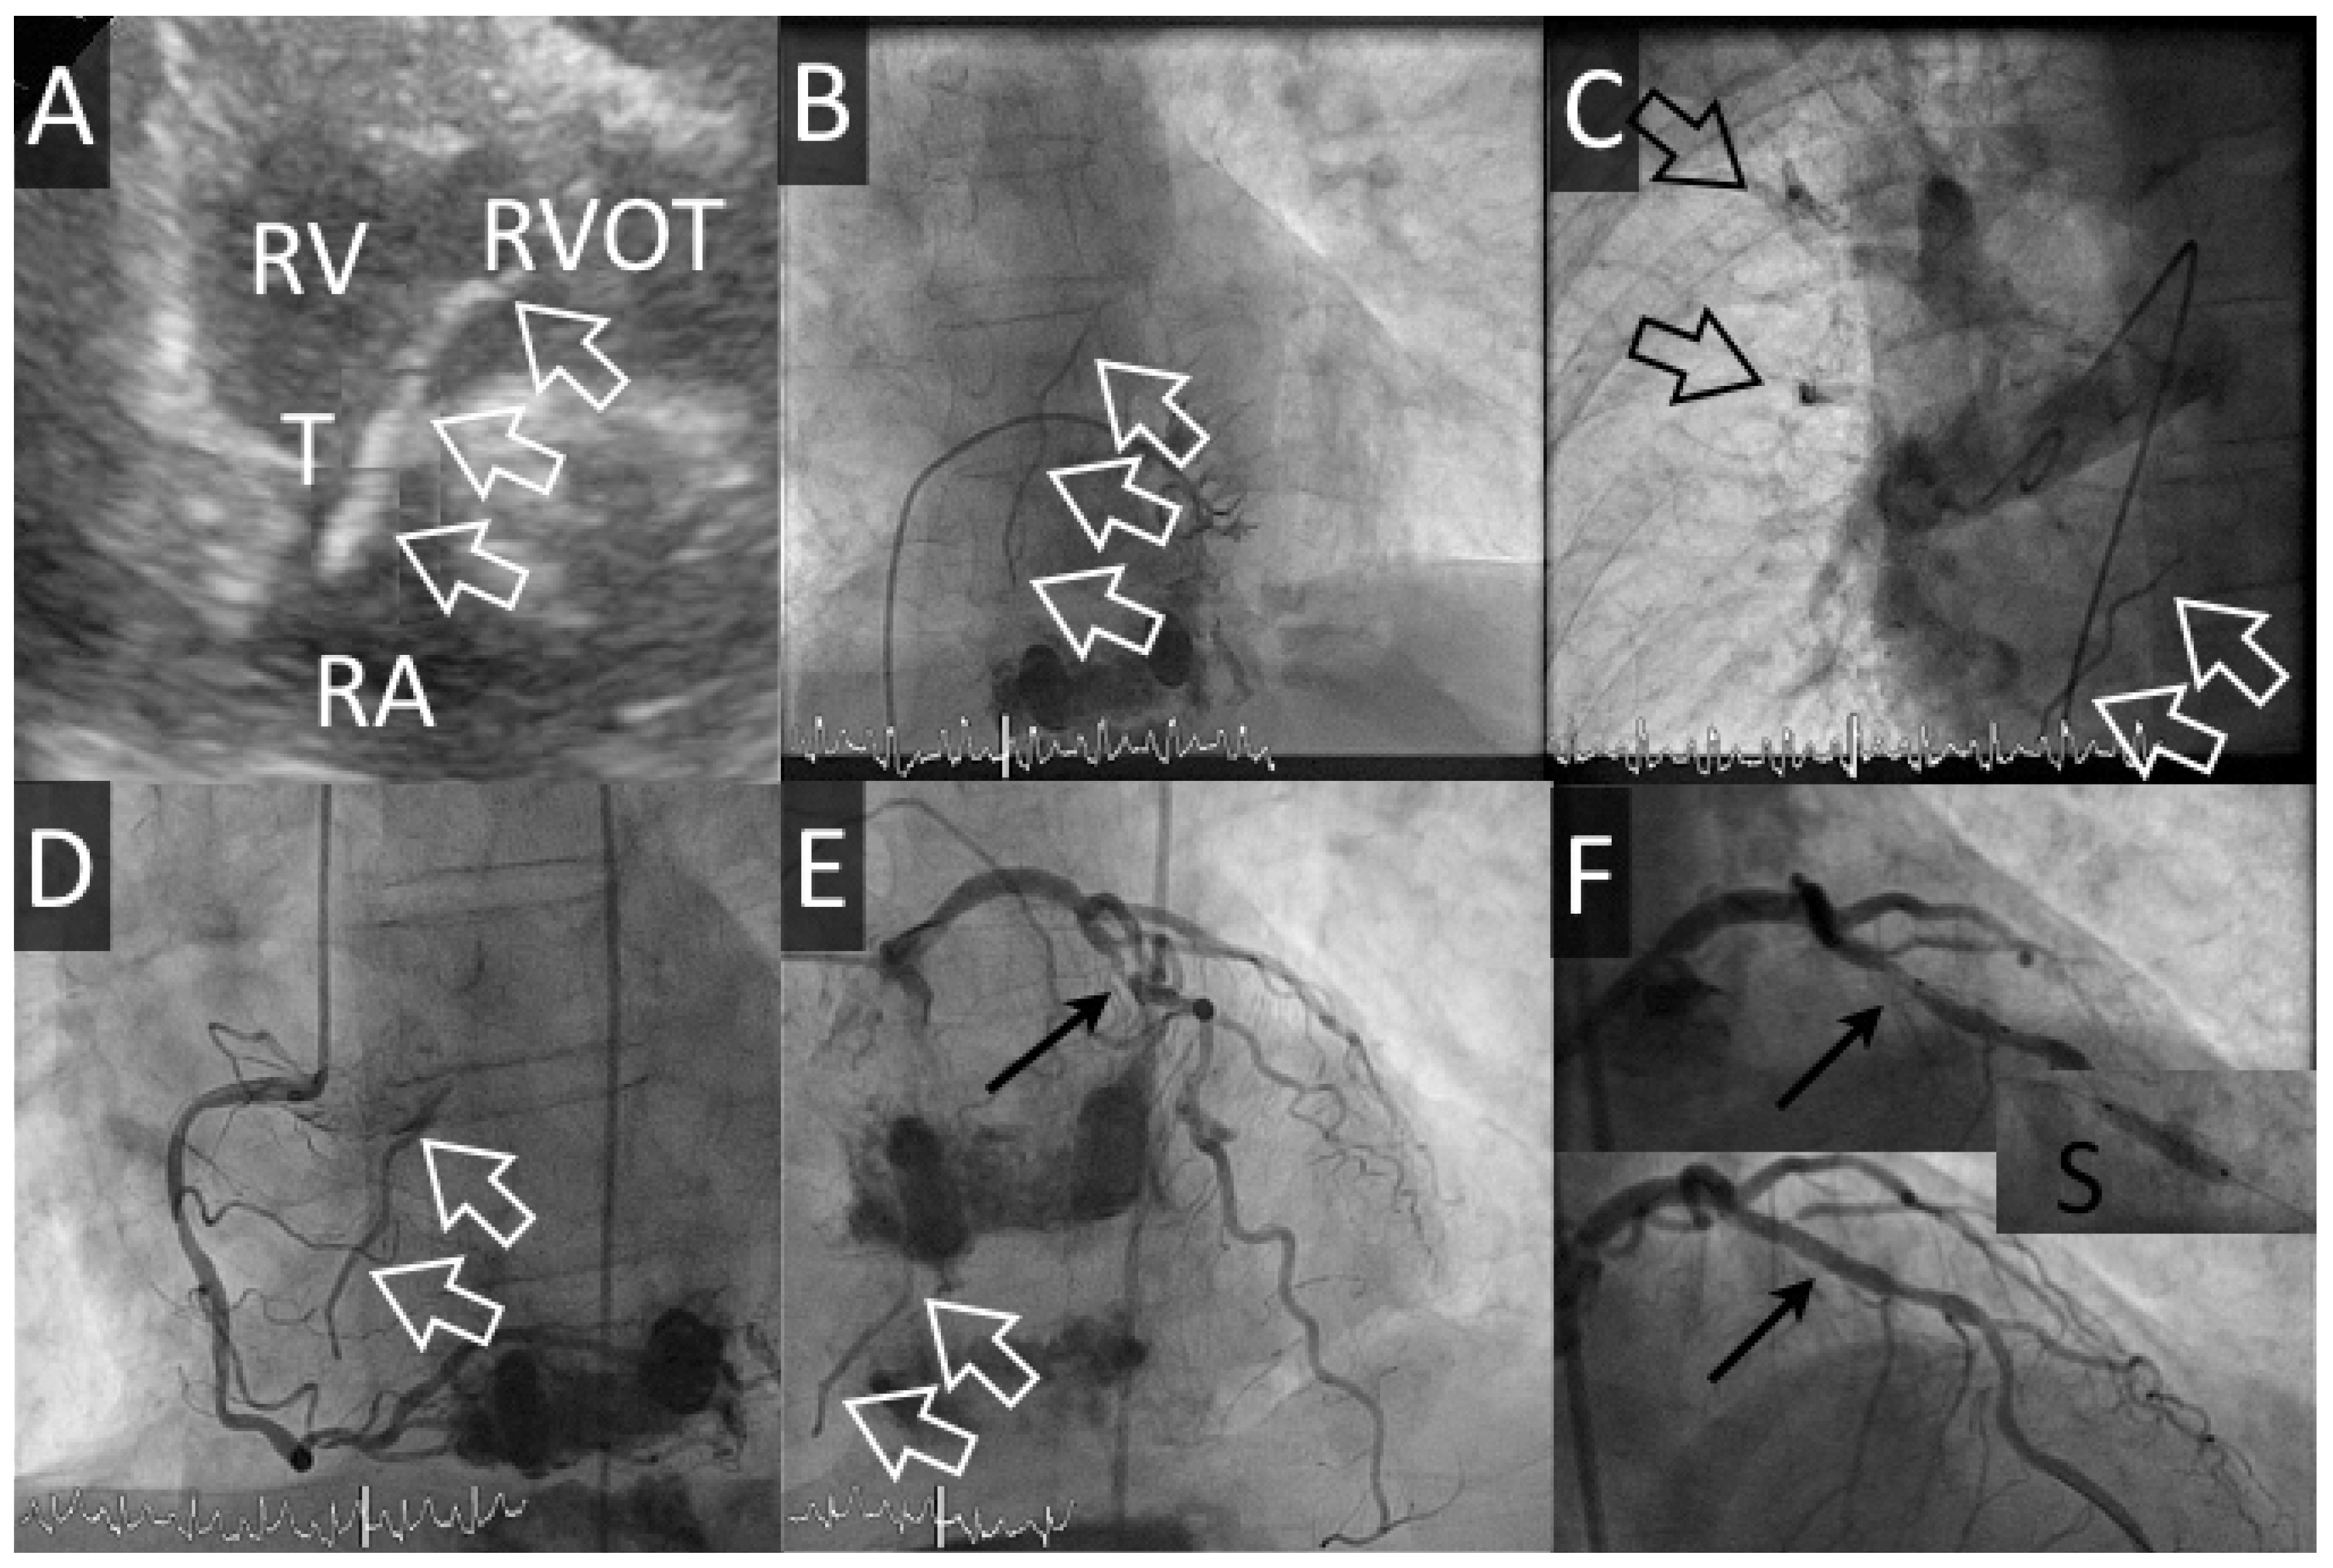

Une patiente de 66 ans avec BPCO Gold IV et oxygénothérapie bénéficie d’une troisième cyphoplastie (dernière cyphoplastie de D11 et D12, 2 mois auparavant) de L1 pour des fractures tassements symptomatiques sur ostéoporose. Durant l’intervention, une fuite de ciment est visualisée dans une veine péri-vertébrale gauche mais n’a pas de conséquence hémodynamique. Environ 5 heures après la fin de l’intervention, la patiente rapporte de vives douleurs latéro-thoraciques gauches associées à une exacerbation de sa dyspnée chronique, une désaturation (SatO2 84%), une hypotension artérielle (101/62 mm Hg) et une tachycardie sinusale (à 104 bpm). L’ECG est inchangé et la troponine-hs est à 30 ng/l (14 < zone grise < 50 ng/l). La radiographie du thorax montre des opacités dans les lobes supérieur et para-hilaire droits. Une échocardiographie démontre de plus un filament au travers de la valve tricuspide. Une coronarographie est effectuée en raison des douleurs thoraciques répondant aux nitrés et non explicables par les emboles de ciment intra-pulmonaires. Cet examen confirme l’embolisation pulmonaire et la présence d’un embole figé en transit au travers de la valve tricuspide. Le cathétérisme cardiaque droit montre une discrète hypertension artérielle pulmonaire (35 mm Hg, probablement chronique sur la BPCO connue). En l’absence de répercussion hémodynamique, un traitement conservateur est proposé et une sténose serrée de l’artère interventriculaire antérieure découverte fortuitement est traitée (2,75/12 mm—Xience Alpine, Abbott Vasc) après discussion avec la patiente. Une triple thérapie par aspirine, clopidogrel et anticoagulation orale est initiée pour un mois, suivi de 5 mois de double antiaggrégation plaquettaire. L’évolution échocardiographique et clinique est simple depuis lors.

Figure 2. Cas #2. Panel A. Echocardiographie transthoracique avec filament de ciment (flèches blanches creuses) de l’oreillette droite (RA) à la chambre de chasse droite (RVOT) au travers de la valve tricuspide (T). Panel B. Le même filament est visible pendant la dextrographie et des emboles périphériques sont visibles pendant l’artériographie pulmonaire (Panel C). Panel D-F: La coronarographie démontre une sténose serrée de l’artère interventriculaire antérieure (flèche noire), qui est traitée en passant par la mise en place d’un stent actif (S) avec bon résultat final.